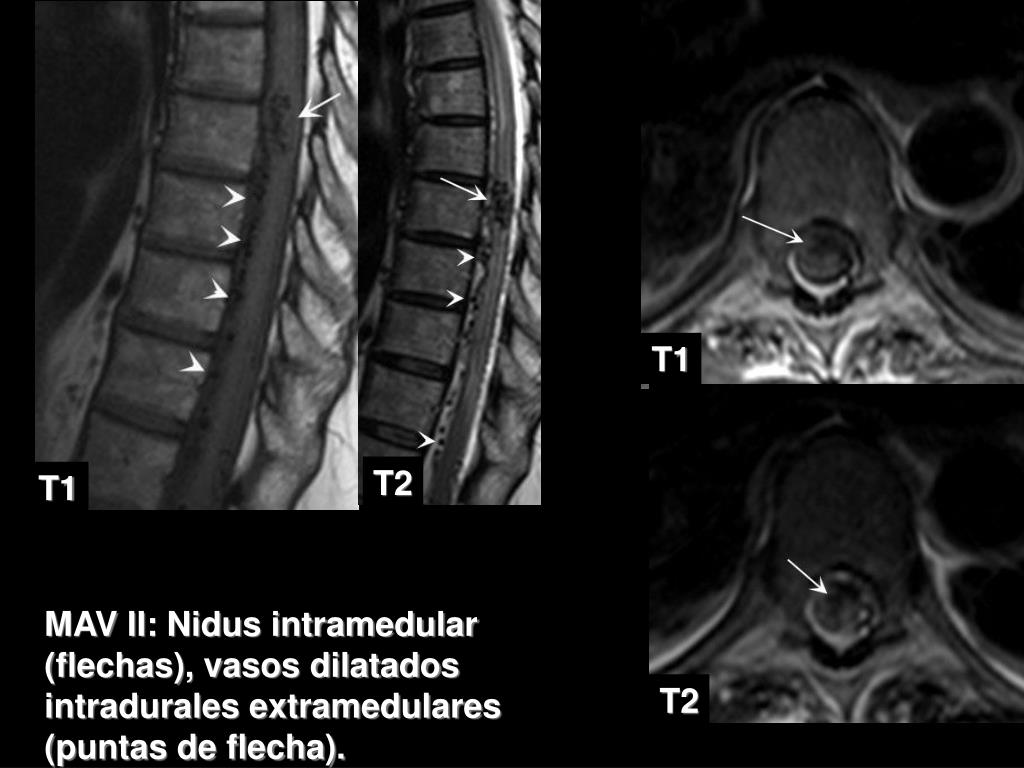

2. T1 T2 T1 MAV II: Nidus intramedular (flechas), vasos dilatados intradurales extramedulares (puntas de flecha). T2